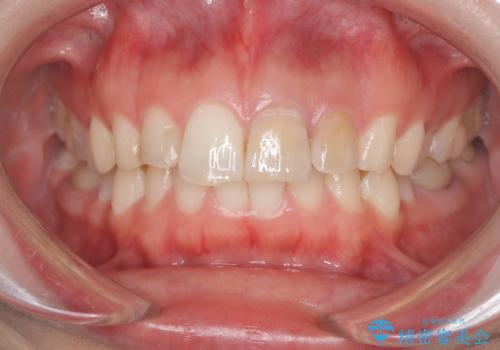

「数日前から前歯に痛みがある」「左上1、2番の色が気になる」

左上1番および2番は失活歯であり、両歯ともに失活に伴う変色を認めました。左上2番に関しては根尖部に透過像を認め、根尖性歯周炎と診断しました。これが前歯部の痛みの原因と考えられました。